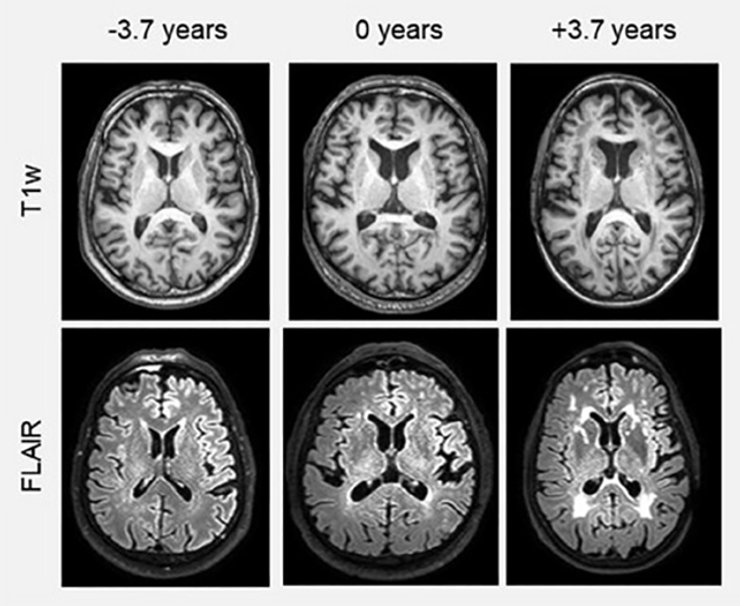

Команда использовала модель глубоко обучения ИИ для оценки возраста мозга с помощью сканирования магнитно-резонансной томографии (МРТ), предварительно обучив модель на более чем 18 000 сканированиях людей без каких-либо когнитивных проблем. Далее информацию из образцов крови сопоставили с оценкой возраста мозга, факторами образа жизни, медицинскими состояниями и результатами когнитивных тестов.